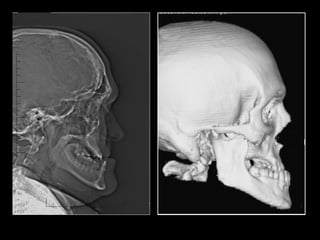

TC 3D

Adquisición de datos Reconstrucción virtual del modelo 3D Validación Validación Producción física del modelo Cirugía de modelo: moldeo placa, osteotomía mandíbula y peroné Esterilización: placa y modelo Uso en quirófano

Mandíbula  sin  relación céntrica Mandíbula  con  relación céntrica Reconstrucción 1ª o 2ª

Mandíbula  con  relación céntrica Reconstrucción  1ª

Adquisición de datos Reconstrucción virtual del modelo 3D Validación Validación Producción física del modelo Cirugía de modelo: moldeo placa, osteotomía mandíbula y peroné. Esterilización: placa y modelo Uso en quirófano

Mandíbula  sin  relación céntrica Reconstrucción  1ª

Adquisición de datos Reconstrucción virtual del modelo 3D Validación Validación Producción física del modelo Cirugía de modelo: moldeo placa, osteotomía mandíbula y peroné, sistema relación. Esterilización: placa y sistema y modelo Uso en quirófano